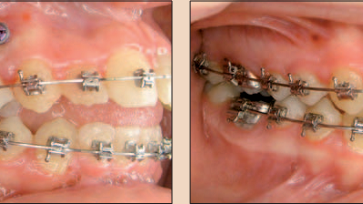

Hình 1a: Di xa răng hàm lớn hàm trên. Vị trí về phía gần của răng #16 và #26, cho thấy thiếu chỗ răng nanh rõ rệt.

Hình 1b, 1c: Khí cụ Walde Frog (Forestadent) neo với 2 mini vít. b). Di xa khoảng 6mm sau 3 tháng, tạo đủ chỗ cho răng nanh sắp thẳng.

Trường hợp đầu tiên (Hình 1a-c) có những vấn đề thường gặp: răng hàm lớn của bệnh nhân di gần đường giữa, dẫn đến thiếu chỗ cho răng nanh phát triển.

Có hai lựa chọn điều trị là nhổ hoặc di xa răng để điều trị trường hợp này, có thể nhận thấy rằng di xa răng hợp lý hơn việc nhổ mất răng.

Khi xem xét ví dụ này, có khả năng lớn phương pháp di xa thông thường sẽ làm nhóm răng trước nhô ra. Có thể tránh được hầu hết hiệu ứng phụ này nếu sử dụng phương pháp cắm ghép mini vít.

Mini vít có thể được cắm ghép ở tiền đình và vòm miệng (như ví dụ này). Cắm vít ở tiền đình (ví dụ giữa các răng hàm nhỏ) thường có hiện tượng mini vít cản trở sự di chuyển của răng. Khi điều này xảy ra, phải tháo bỏ mini vít và dùng dạng neo chặn thông thường (VD: dùng chỉ thép buộc khối các răng lại với nhau).